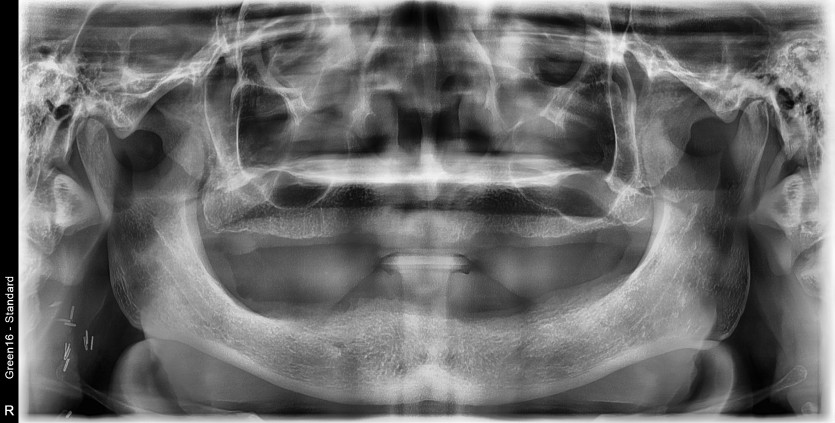

만 72세 전체 임플란트 증례

전체 임플란트 증례입니다.

18개의 임플란트로 완성하였습니다.